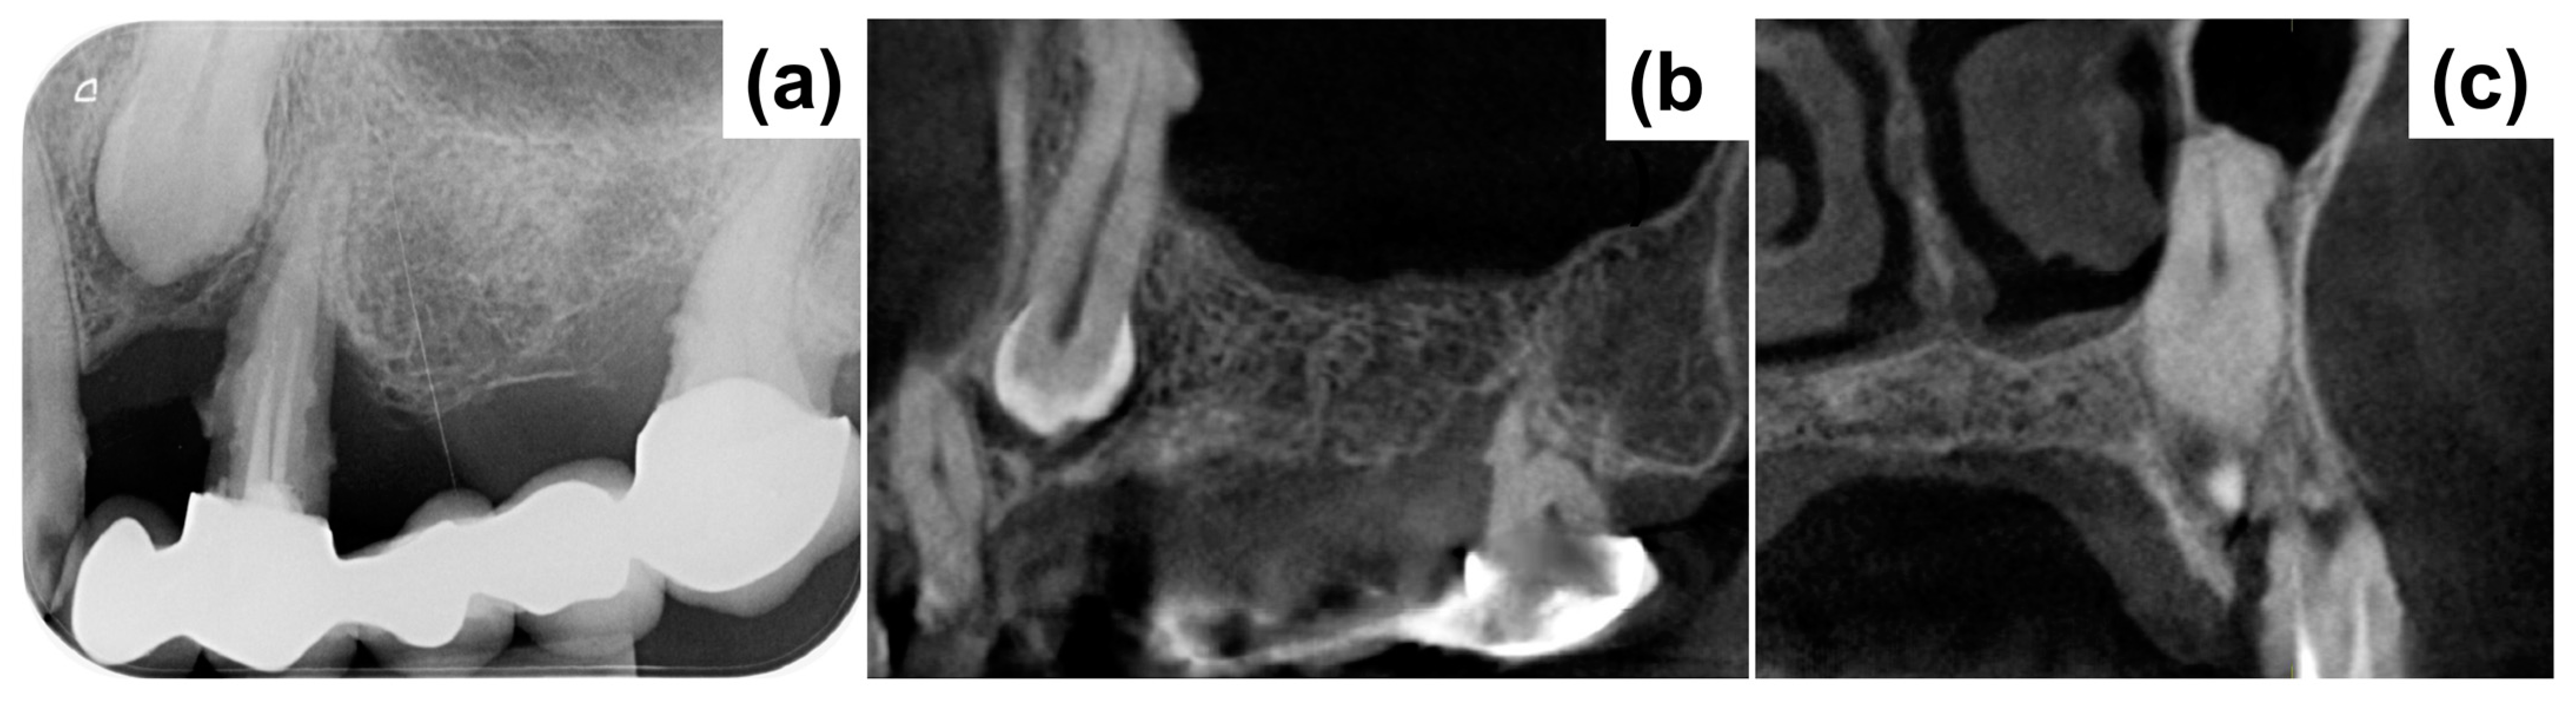

2. Case Presentation